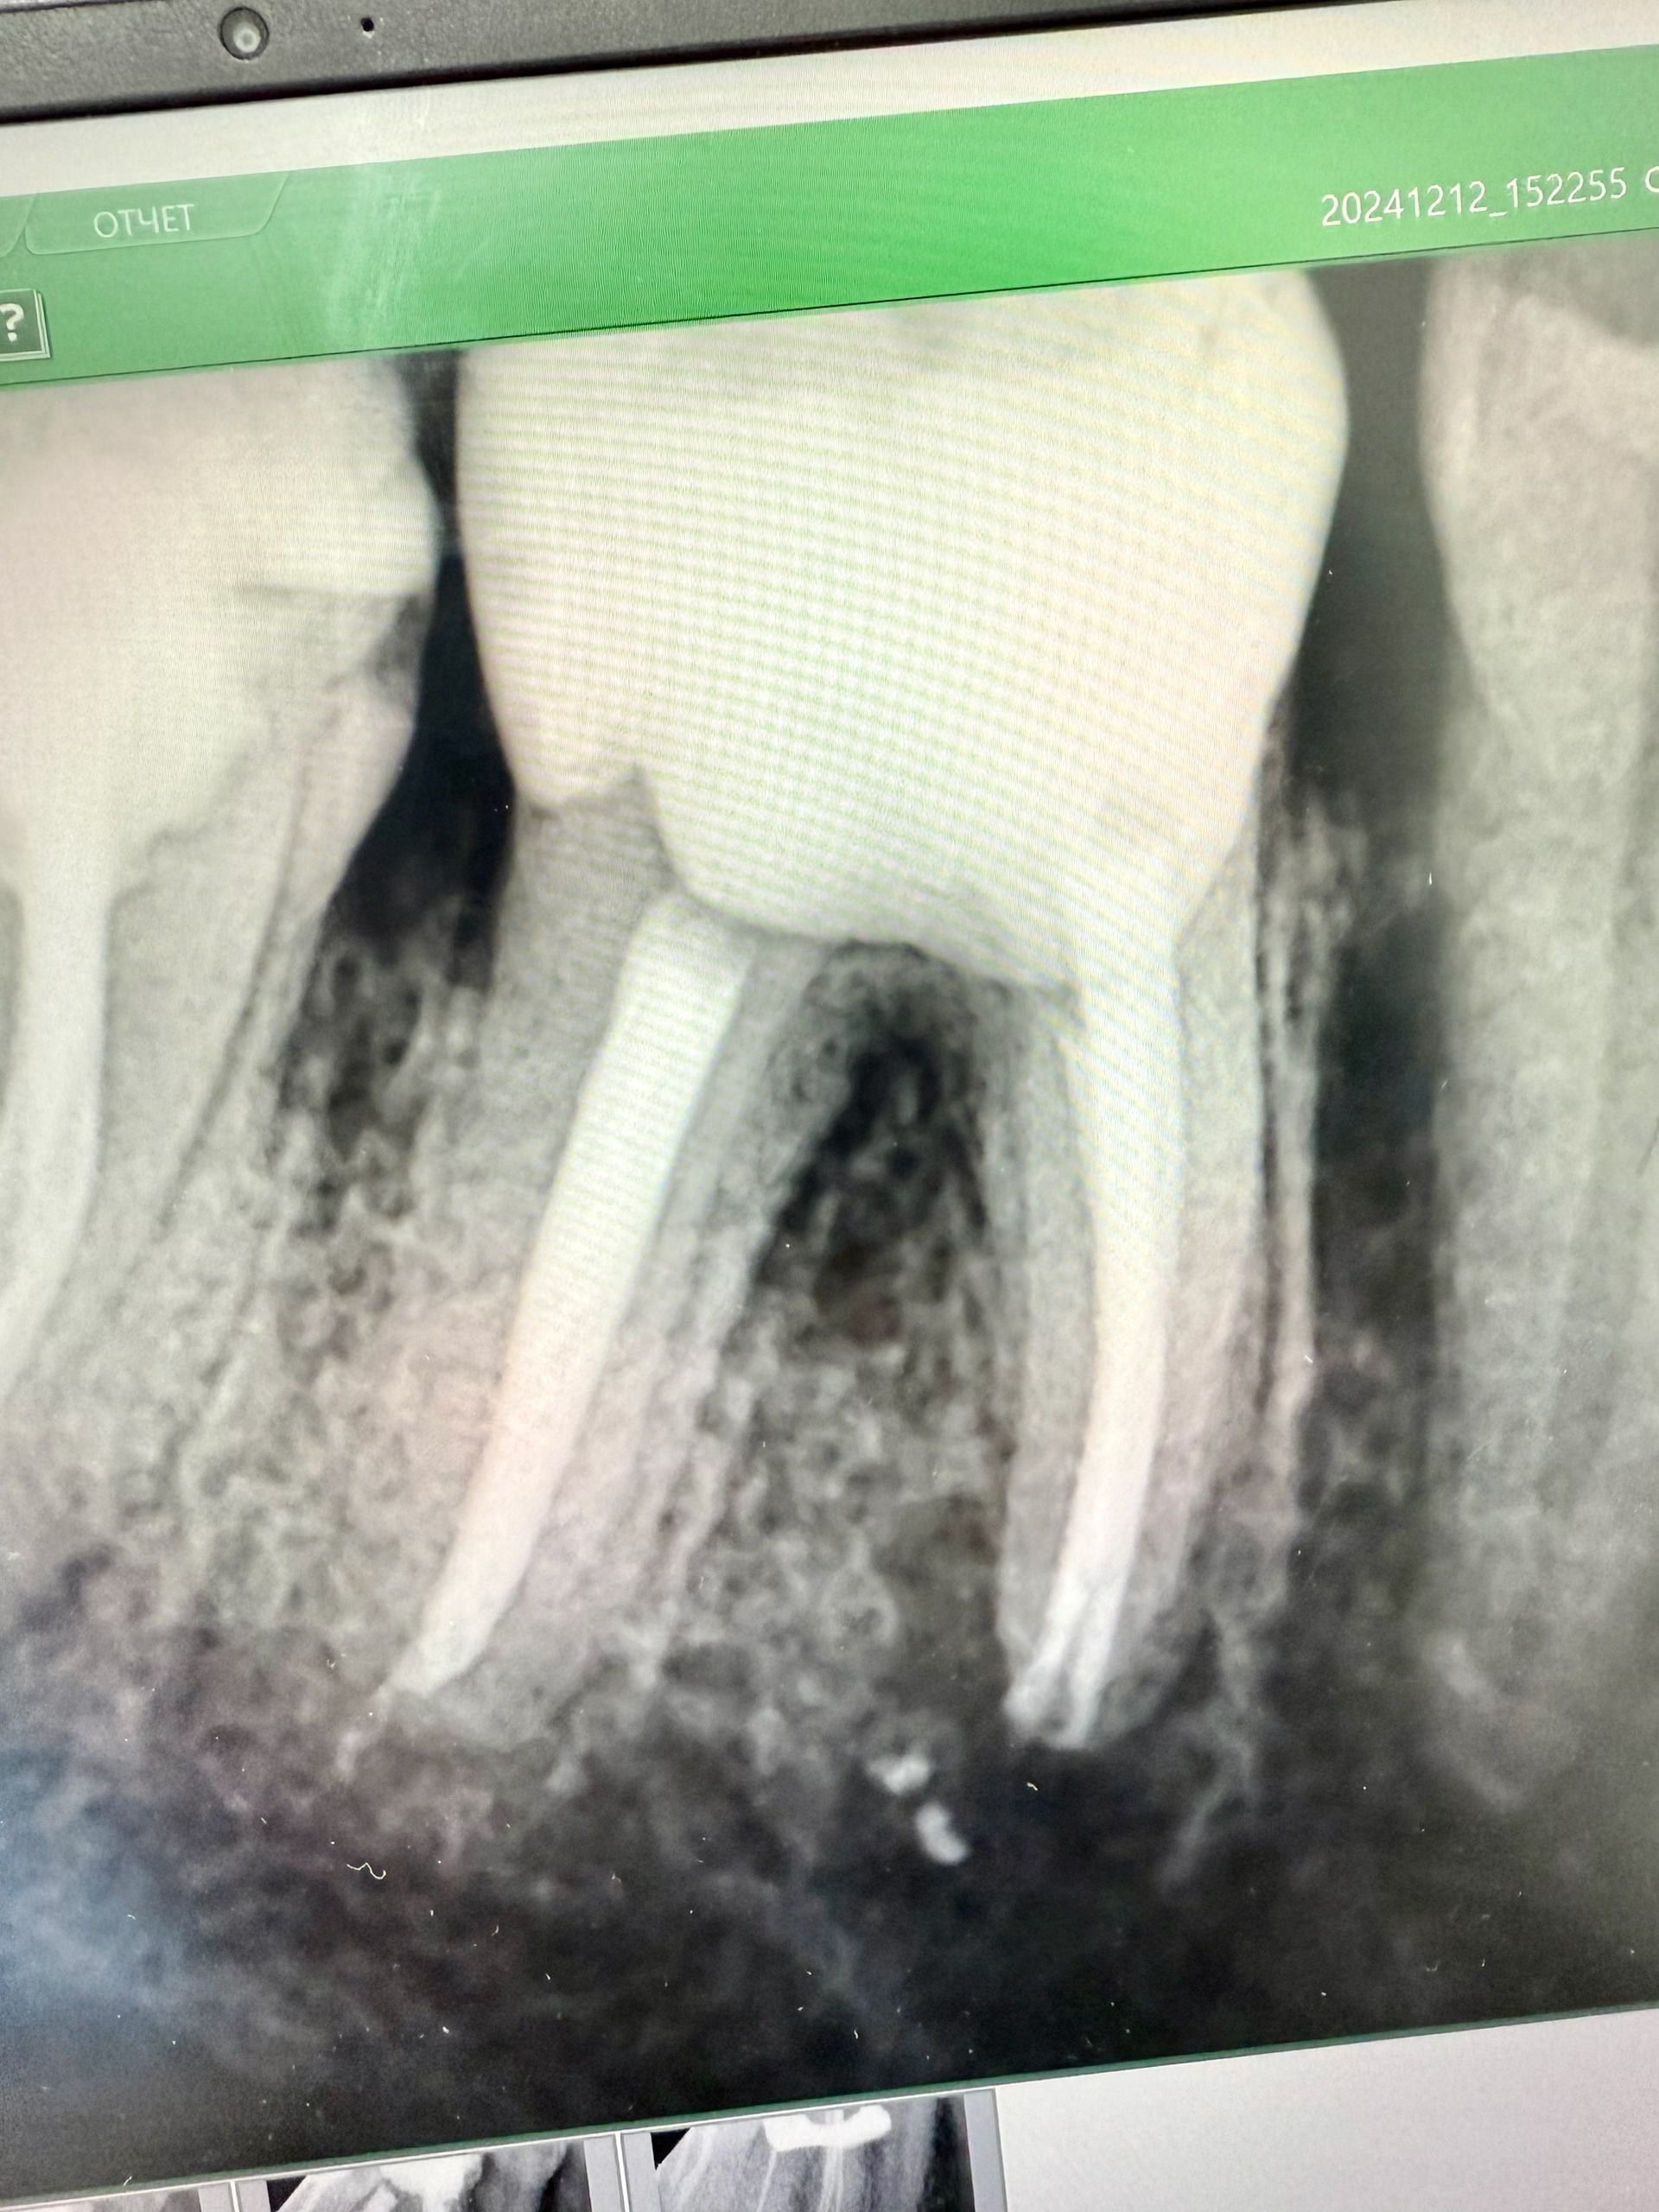

Всем привет! Сегодня, наконец, завершил этот случай, особенностью является то, что в зубе №36 (апикальный периодонтит).

1. Были пропущены два канала: мезиально щёчный и мезиально срединный. А также то, что все они отдельные каналы.

2. Пациентка пришла в обострение, здесь была и экспресс-диагностика на трещину (времени было мало, а пломба огромная) и разрез хирурга.

3. Но мы его успокоили, перелечили и отправили на временной коронки! Автор: Евгений Никулин